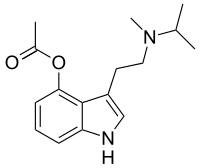

Substituted tryptamines, or serotonin analogues, are organic compounds which may be thought of as being derived from tryptamine itself. The molecular structures of all tryptamines contain an indole ring, joined to an amino (NH2) group via an ethyl (−CH2–CH2−) sidechain. In substituted tryptamines, the indole ring, sidechain, and/or amino group are modified by substituting another group for one of the hydrogen (H) atoms.

| 4-AcO-DMT | artificial | 4-OCOCH3 | CH3 | CH3 | 4-acetoxy-N,N-dimethyltryptamine | 92292-84-7 |

| 4-PrO-DMT | artificial | 4-OCOCH2CH3 | CH3 | CH3 | 4-propionyloxy-N,N-dimethyltryptamine | 1373882-11-1 |

| 4-Acetoxy-MET | artificial | 4-OCOCH3 | CH3 | CH2CH3 | 4-acetoxy-N-methyl-N-ethyltryptamine | 1445751-40-5 |

| 4-Acetoxy-DET | artificial | 4-OCOCH3 | CH2CH3 | CH2CH3 | 4-acetoxy-N,N-diethyltryptamine | 1135424-15-5 |

| 4-Acetoxy-MiPT | artificial | 4-OCOCH3 | CH3 | CH(CH3)2 | 4-acetoxy-N-methyl-N-isopropyltryptamine | 1024612-25-6 |

| 4-AcO-DPT | artificial | 4-OCOCH3 | CH2CH2CH3 | CH2CH2CH3 | 4-acetoxy-N,N-dipropyltryptamine | 1445751-75-6 |